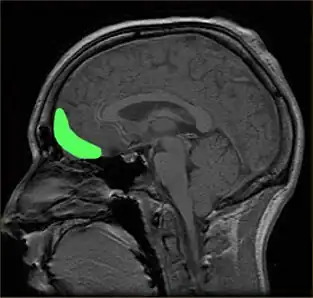

Areas of the brain linked to the processing of visual aesthetics

Aesthetic perception relies heavily on the processing by the visual centers in the brain such as the V1 cortex. Signals from V1 are distributed to various specialized areas of the brain.[38] There is no single area where all specialized visual circuitry connect, reducing the chances of determining a single neural center responsible for aesthetics, rather a neural network is more likely.[6] Therefore, the visual brain consists of several parallel multistage processing systems, each specialized in a given task such as color or motion. Functional specializations of the visual brain are already known.[32]

Prefrontal cortex

The prefrontal cortex is previously known for its roles in the perception of colored objects, decision making, and memory. Recent studies have also linked it to the conscious aesthetic experience because it is activated during aesthetic tasks such as determining the appeal of a visual stimuli. This may be because a judgment is needed, requiring visiospatial memory. In a study performed by Zeki and Kawabata, it was found that the medial orbito-frontal cortex (mOFC) is involved in the judgment of whether a painting is beautiful or not.[32] There is high activation in this region when a person views paintings which they consider beautiful. Other evidence shows that this same area is active during the experience of beauty derived from different sources,[42] including musical beauty[43] and moral beauty,[44] and even mathematical beauty.[45] Interestingly, experience of the sublime, as opposed to the beautiful, results in a different pattern of brain activity;[46] moreover, where it comes to judgment, although aesthetic and perceptual judgments leads t activity in the same brain areas, the pattern of activity is also different between the two, one of the most marked differences being the involvement of mOFC in aesthetic, but not in perceptual, judgments.[47] Surprisingly, when a person views a painting which they consider ugly, no separate structures are activated. Therefore, it is proposed that changes in the intensity of activation in the orbito-frontal cortex correlate with the determination of beauty (higher activation) or ugliness (lower activation). Additionally, the medial OFC has been found to respond aesthetics in terms of the context of which it is presented, such as text or other descriptions about the artwork. The current evidence linking the OFC to attributed hedonistic values across gustatory, olfactory, and visual modalities, suggests that the OFC is a common center for the assessment of a stimulus's value.[35] The perception of aesthetics for these areas must be due to the activation of the brain's reward system with a certain intensity.

Additionally, the prefrontal dorsalateral cortex (PDC) is selectively activated only by stimuli considered beautiful whereas prefrontal activity as a whole is activated during the judgment of both pleasing and unpleasing stimuli.[6] The prefrontal cortex may be generally activated for directing the attention of the cognitive and perceptual mechanisms towards aesthetic perception in viewers untrained in visual arts.[17] In other words, related directly to a person viewing art from an aesthetic perception due to the top-down control of their cognition. The lateral prefrontal cortex is shown to be linked to higher order self-referential procession and the evaluation of internally generated information. The left lateral PFC, Brodmann area 10, may be involved in maintaining attention on the execution of internally generated goals associated with approaching art from an aesthetic orientation.[17] As previously mentioned, directing of attention towards aesthetics may have evolutionary significance.